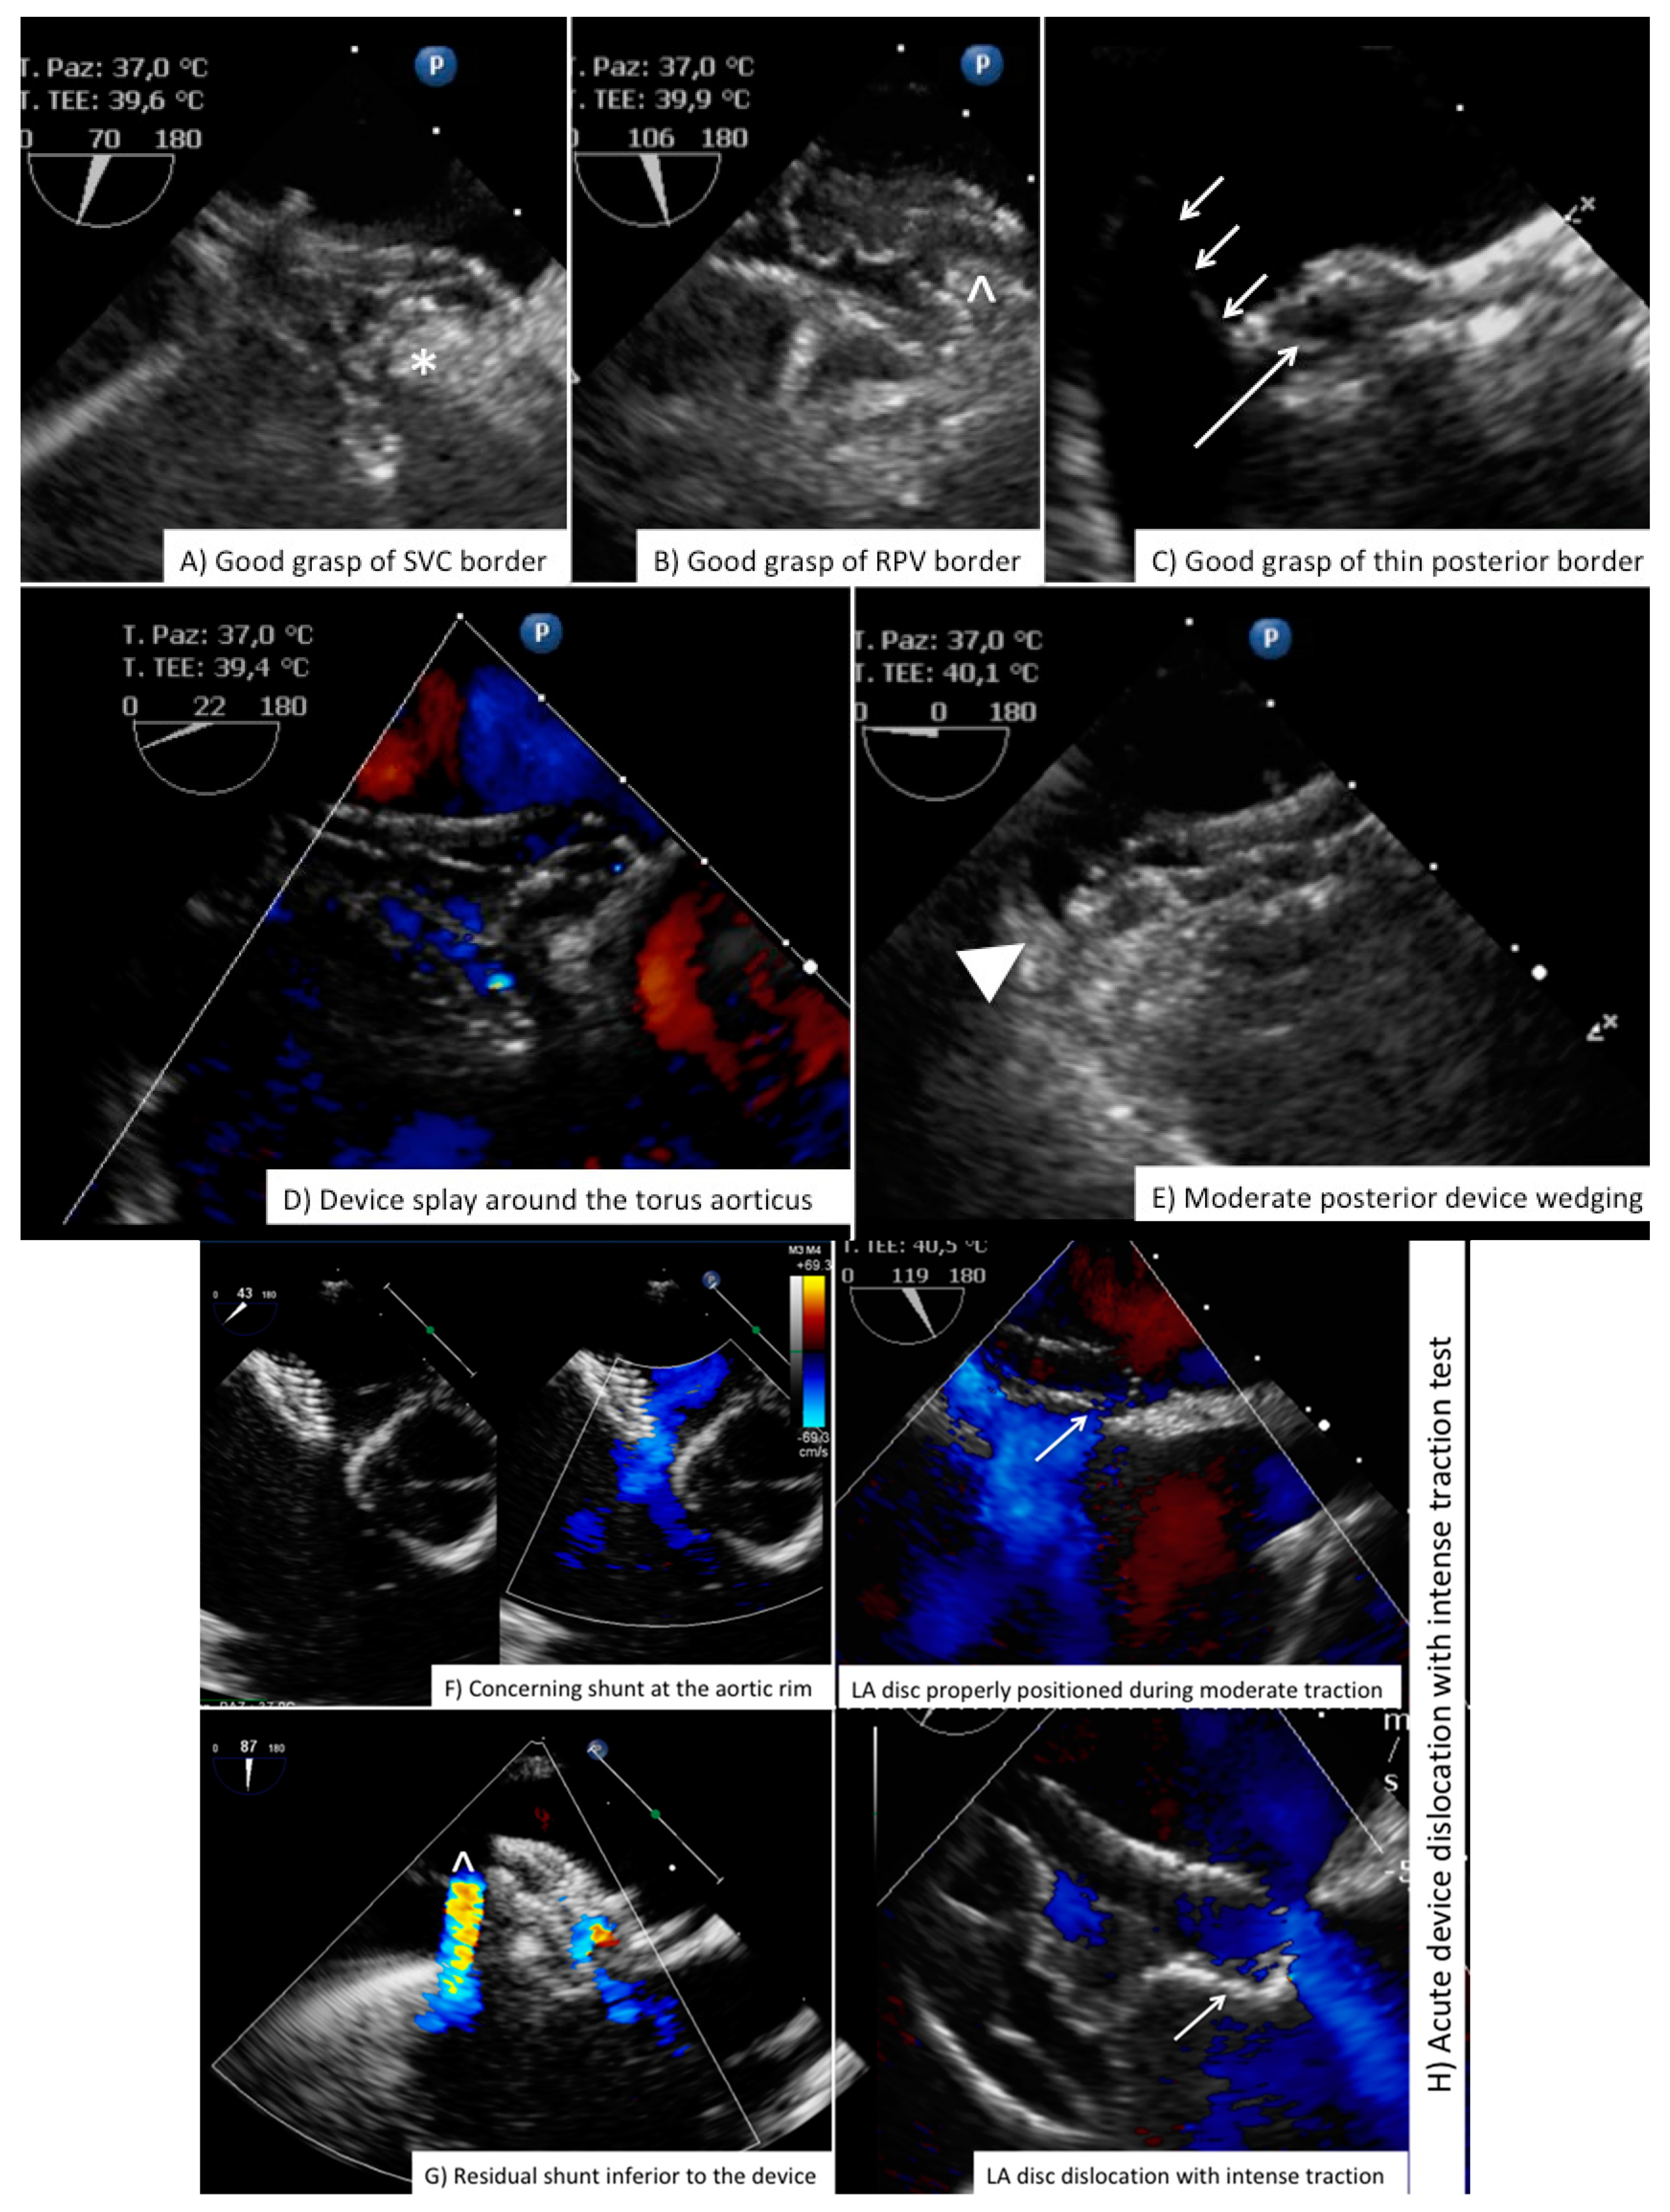

Although, some intradevice shunt is frequently seen and it is often due to tension from the delivery cable or securing lines, there are some subtle echo markers of suboptimal position that should be always identified: (1) incomplete grasp on the superior or postero-inferior border; (2) residual shunt viewed at 45°–60° between the device and torus aorticus at baseline and under gentle device traction; (3) shifting device position during pull and push maneuver; (4) interference with mitral valve/superior vena cava/inferior vena cava/coronary sinus; (5) severe device wedging (device not moving throughout the cardiac cycle but entangled between the anterior/aortic and the posterior rim) with direct contact between device and surrounding atrial wall or structures (Figure 8, Videos S6–S8 Online Supplementary Material). In all these cases, an open discussion with interventionalist must occur and potential device repositioning or change may be necessary. After device release an additional complete device evaluation is important because quite often there is some shifting in device positioning after cable or secure lines release, that is usually allowing the device to fit in a more “anatomical” position. Again, we reinforce the importance of final transthoracic 4-chamber view imaging to have a comparison frame if any question of late malposition should arise.

Figure 8. Complication after ASD closure. Examples of complication or sub-optimal procedural result after ASD closure. Please note in (F), the presence of shunt between the device and torus aorticus is to be compared with normal “intra-device” flow seen in (G). Device embolization to the left ventricular cavity is shown in (I,J). ASD = secundum type Atrial Septal Defect; LA = Left Atrium; RPV = Right Pulmonary Valve; SVC = Superior Vena Cava.